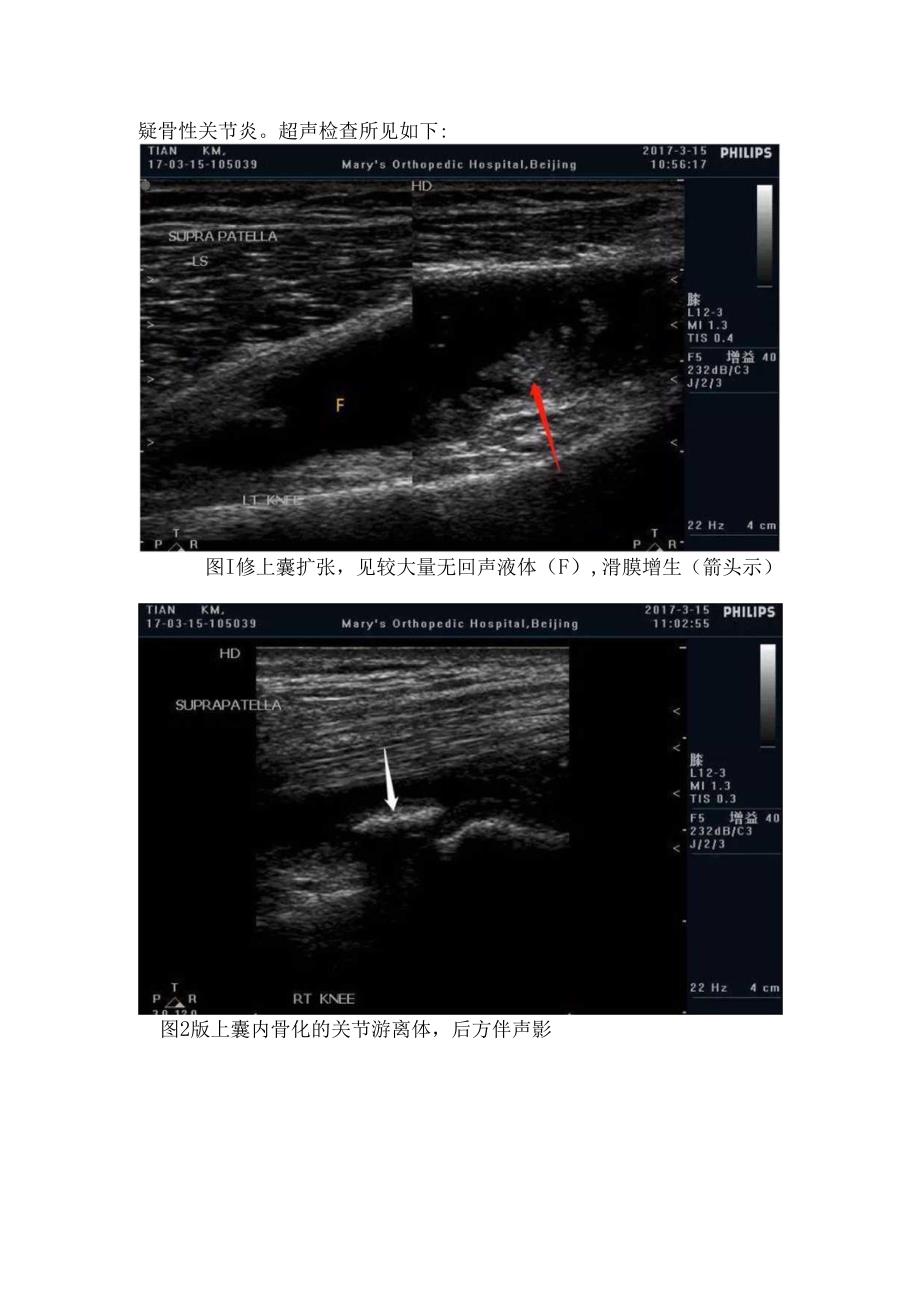

2、。内侧区:主要包括膝内侧副韧带,内侧半月板和鹅足腱止点等。内侧半月板位于股骨与胫骨之间,因其为纤维软骨,超声上正常呈高回声,纵切面上呈三角形,尖部指向关节内。外侧区:包括膝外侧副韧带和外侧半月板。膝后区:除胴动脉、胴静脉和胫神经外,还应重点注意腓肠肌内侧头-半膜肌腱滑囊,正常情况下,该滑囊仅有少量滑液,滑囊异常扩张时,形成Baker囊肿。病例分享老年女性患者,主诉双侧膝关节肿胀、疼痛并活动障碍。临床怀疑骨性关节炎。超声检查所见如下:图I修上囊扩张,见较大量无回声液体(F),滑膜增生(箭头示)图2版上囊内骨化的关节游离体,后方伴声影PINGJY,18-02-14-1517342018214PHI

3、1.IPS15:27:42MarysOrthopedicHospita1.BeijingF5增益35232dBC3J/2/3RT1.AT23Hz3cm图3和图4示膝关节内侧和外侧关节两端骨赘形成(白色箭头),关节间隙变窄,半月板明显外突向关节囊内(红色箭头)ZHAOBS,1812-06-1131232018-12-6PHI1.IPS11:35:49MarysOrthopedicHospitaIfBeijingH5增益40-232dBC3J/2/311Hz4cm图5股骨关节透明软骨变薄(箭头示),厚度不均匀PlNGJY,18021A1517342018-2-14PHI1.IPS15:26:53M